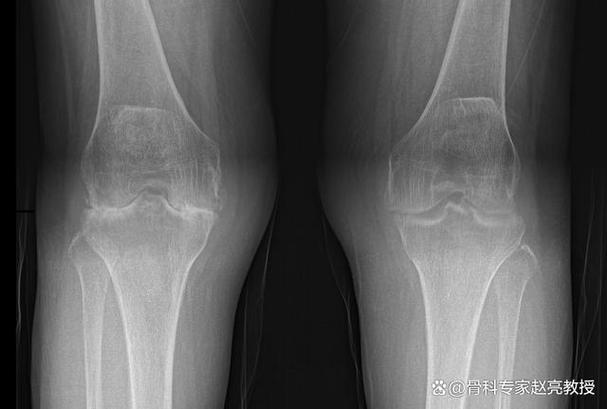

- 膝关节:承受着身体的重量,是RA最常累及的大关节之一,严重的膝关节破坏会导致患者无法站立和行走。